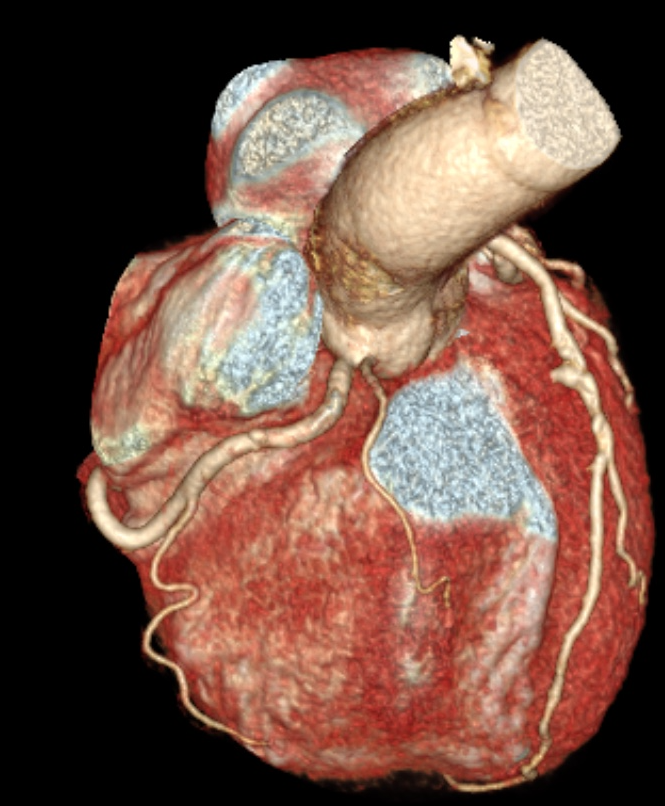

Η μη επεμβατική υψηλής ανάλυσης αξονική τομογραφία (CCTA) χρησιμοποιείται για την καλύτερη κατανόηση της ανατομίας των στεφανιαίων αγγεία και των αθηρωματικών τους πλακών. Η CCTA βοηθά σημαντικά στον σωστό προγραμματισμό πριν από την αγγειοπλαστική (PCI), καθώς οι αρτηρίες της καρδιάς μπορεί να διαφέρουν σημαντικά από ασθενή σε ασθενή.